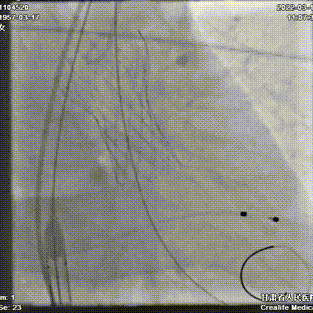

第一次定位释放

第一次释放后位置尚可

静待5分钟后位置明显下滑

回收调整超硬导丝后,再次定位

逐步释放瓣膜,工作位位置理想

工作位造影

瓣膜充分膨胀,完全释放

植入后位置理想,无反流